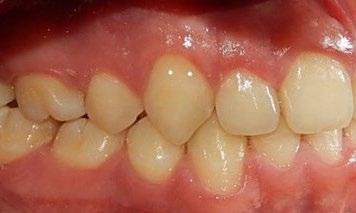

Se presenta un paciente de 18 años de edad que refiere tener hemofilia tipo A, moderado grado V. En los estudios de inicio extraorales, se observa en la Figura 1 el frente, sonrisa y perfil. En la radiografía lateral de inicio (Figura 2) se evidencian el overjet y overbite reducidos, clase I esquelética, hiperdivergencia y biprotrusión dentoalveolar.

En los estudios intraorales, las fotografías iniciales muestran clase I canina y molar bilateral, mordida anterior abierta, apiñamiento leve superior e inferior, y líneas medias dentales

desviadas. En las Figuras 4, 5 y 6 se observa la forma de las arcadas superior e inferior.

Figura 4. Lateral derecha.